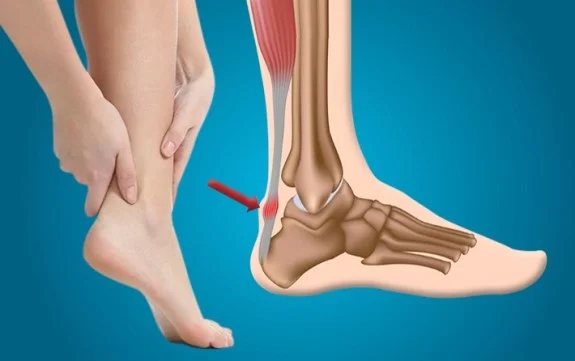

Os problemas no tornozelo são bastante comuns e podem afetar a qualidade de vida de muitas pessoas. Entre os principais problemas que envolvem essa articulação, destacam-se a tendinite do tendão de Aquiles e a entorse de tornozelo. Ambos são distúrbios que envolvem dor, inflamação e, em muitos casos, dificuldade de movimento, sendo resultantes de esforços excessivos ou traumas diretos.

Tendinite do Tendão de Aquiles

As tendinites do tendão de Aquiles, também conhecido como tendão calcâneo, são uma das lesões mais frequentes por uso excessivo do tornozelo e do pé. Essa patologia é mais provável de acontecer em indivíduos que participam de atividades físicas relacionadas a corrida e saltos.

Até cerca de 10% dos corredores recreativos e 5% dos atletas profissionais podem encerrar suas atividades devido a esse problema!!! Essa patologia pode estar relacionada inclusive a rotura do tendão.

A Tendinite do Tendão do Aquiles (crônica) é mais comum em indivíduos idosos do que na população mais jovem. Essa lesão é classicamente dividida em 2 tipos principais:

- Aa tendinopatia insercional, aquela que acontece na região onde o tendão se insere no osso e a não insercional, que está relacionada a inflamação e degeneração no corpo do tendão, como mostram as imagens de ressonância magnética na figura abaixo. A tendinopatia insercional tende a ocorrer em pessoas mais ativas

- A tendinte não insercional do tendão tende a ocorrer em pessoas mais velhas, menos ativas e com excesso de peso.